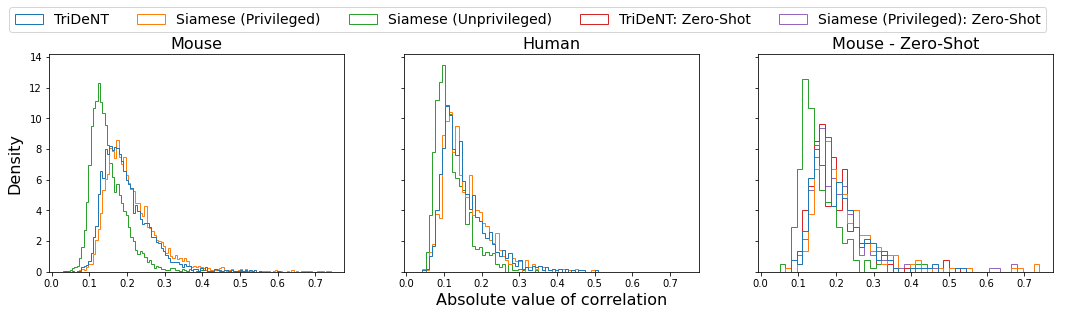

To assess the level of information shared between the transcriptomic results and the representations of the H&E patches, we investigate the cross-correlation between elements of the representations and the gene counts for each matching patch. We calculate the cross-correlation across the validation set between each element in the representations and the count for each gene, and for each gene take the correlation of the corresponding element with the maximum correlation or minimum anti-correlation, whichever has the greater absolute value. This maximum/minimum is chosen because the vast majority of elements will not correlate with any given gene, and the absolute value is taken because the sign of the element is arbitrary, so correlation and anti-correlation are equivalent. We use the absolute value of the correlation for the element selected for each gene, and use these to generate the histograms in Figure 3(a). It is clear that privileged training obtains representations which are far more correlated to the gene counts than unprivileged training, with minimal differences in the correlations between TriDeNT ♆ and Siamese approaches. This implies that the models have learned equivalently informative representations about the coarse-grained features of the genes. Figure 3(c) demonstrates that the correlation strength is significantly greater for TriDeNT ♆ compared to an unprivileged Siamese model, and Figures S3 and S4 show the relationships between the gene correlations of representations from TriDeNT ♆, Siamese methods, and supervised learning. Figures S5 and S6 show the geneset enrichment for each method, demonstrating that TriDeNT ♆ captures more meaninful interrelationships that are more informative about the relationship between tissue morphology and gene expression than unsupervised Siamese models. This is especially important for scientific discovery, as these analyses are used to generate hypotheses for further research. Figure S7 shows UMAP projections of the representation space coloured by genotype and gene, to illustrate that TriDeNT ♆ identifies distinct morphological clusters which are not found by unprivileged Siamese models. Figure 3(a) also shows that the findings are robust to human and mouse datasets, indicating the generality of the method.

We also demonstrate the correlations of the model’s representations with genes unseen during the self-supervised phase of training (Figure 3(a)). We find that the model is not simply overfitting on the given genes, as these genes are not present in the training data, yet the privileged models still demonstrate greater correlation with their counts than an unprivileged approach.